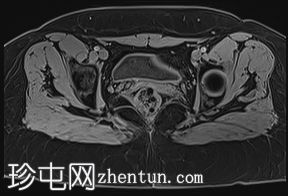

轴位

STIR序列

子宫外底轮廓清晰,肌层较厚,将子宫内膜腔分隔成两个腔,纤维层较薄,向下延伸至宫颈外口。子宫内膜厚度正常,两个子宫腔交界区清晰,未见明显的实性局灶性病变。

本病例展示了典型的纵隔子宫影像学表现:增厚的肌层隔膜将子宫内膜腔分隔成两个腔,并有一层薄的纤维隔膜延伸至子宫颈外口水平,符合完全纵隔子宫的特征。

在MRI图像上,纵隔子宫通常大小正常,但每个子宫腔的形态均小于正常子宫腔。

隔膜可能由纤维组织(T2信号低)、肌层组织(中等信号)或两者共同构成,如本病例所示。